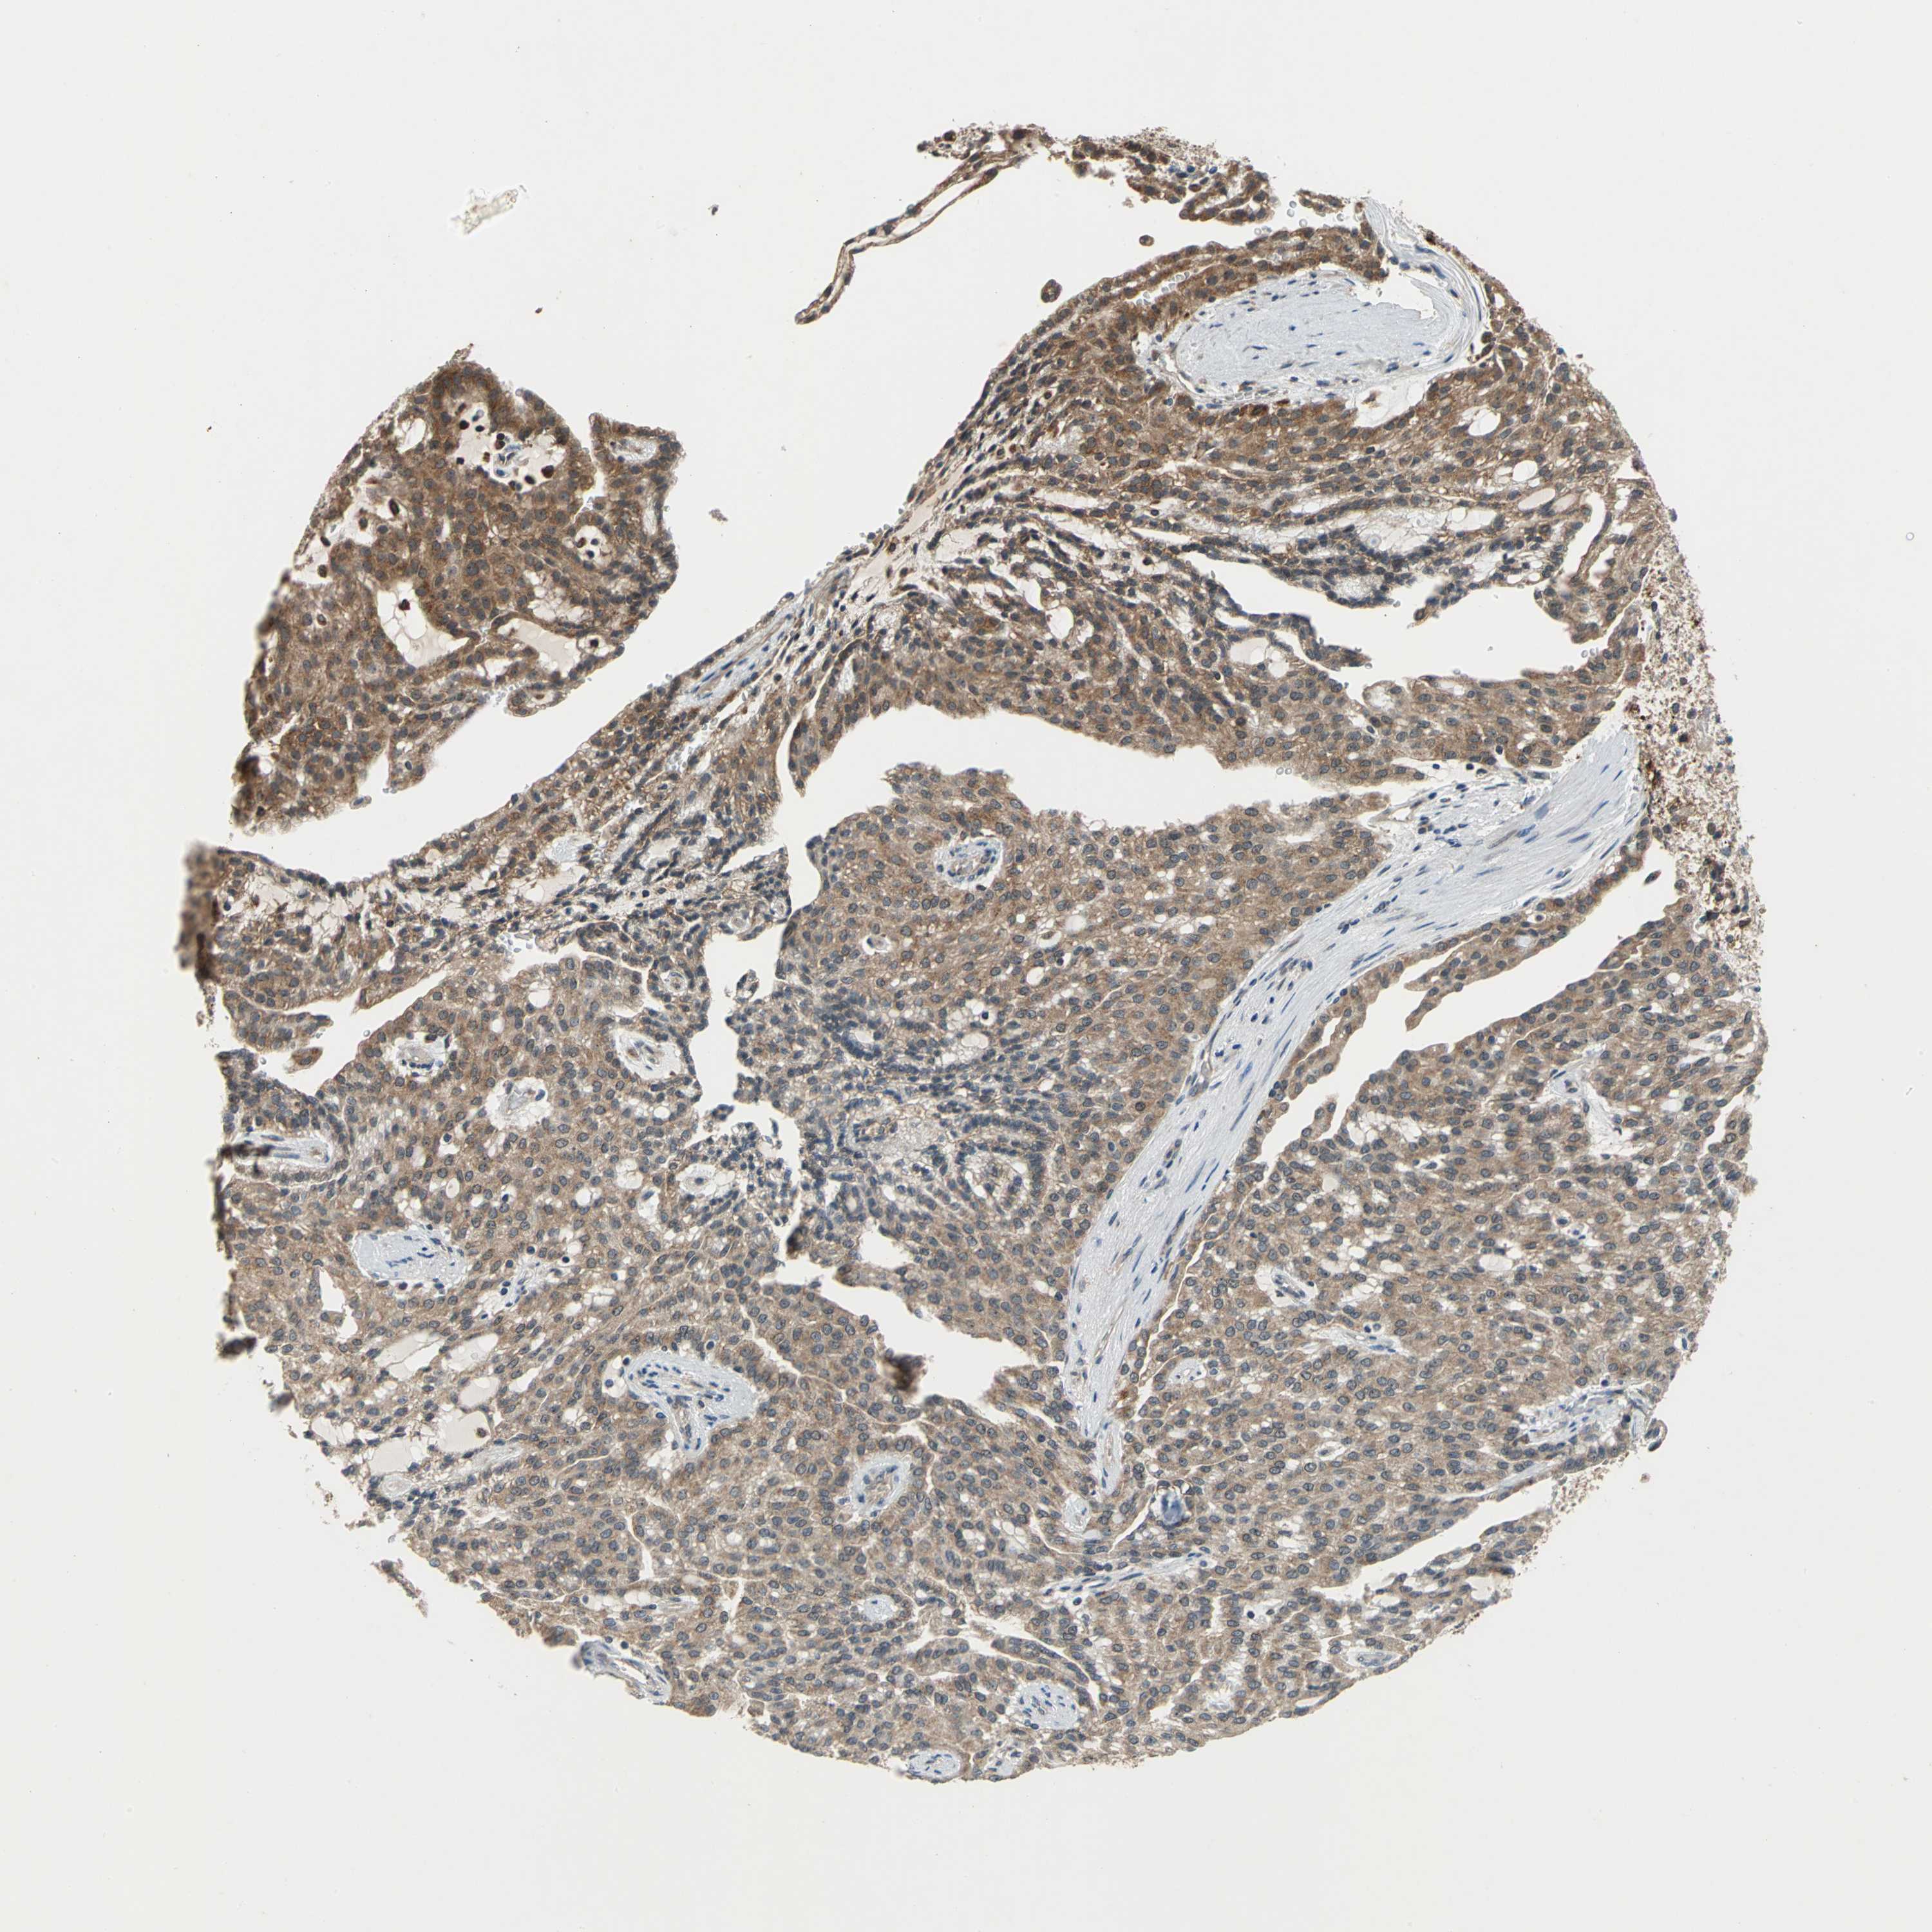

CANCER RENAL CANCER Show tissue menu

KICH TCGA KIRC TCGA KIRC VALIDATION KIRP TCGA PROTEIN RCC CPTAC PROTEIN EXPRESSION